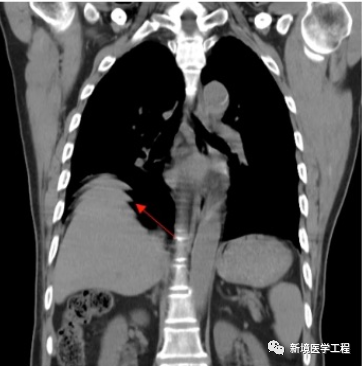

各种成像模式的原理和伪像发生的机制

伪像常见的表现机制;